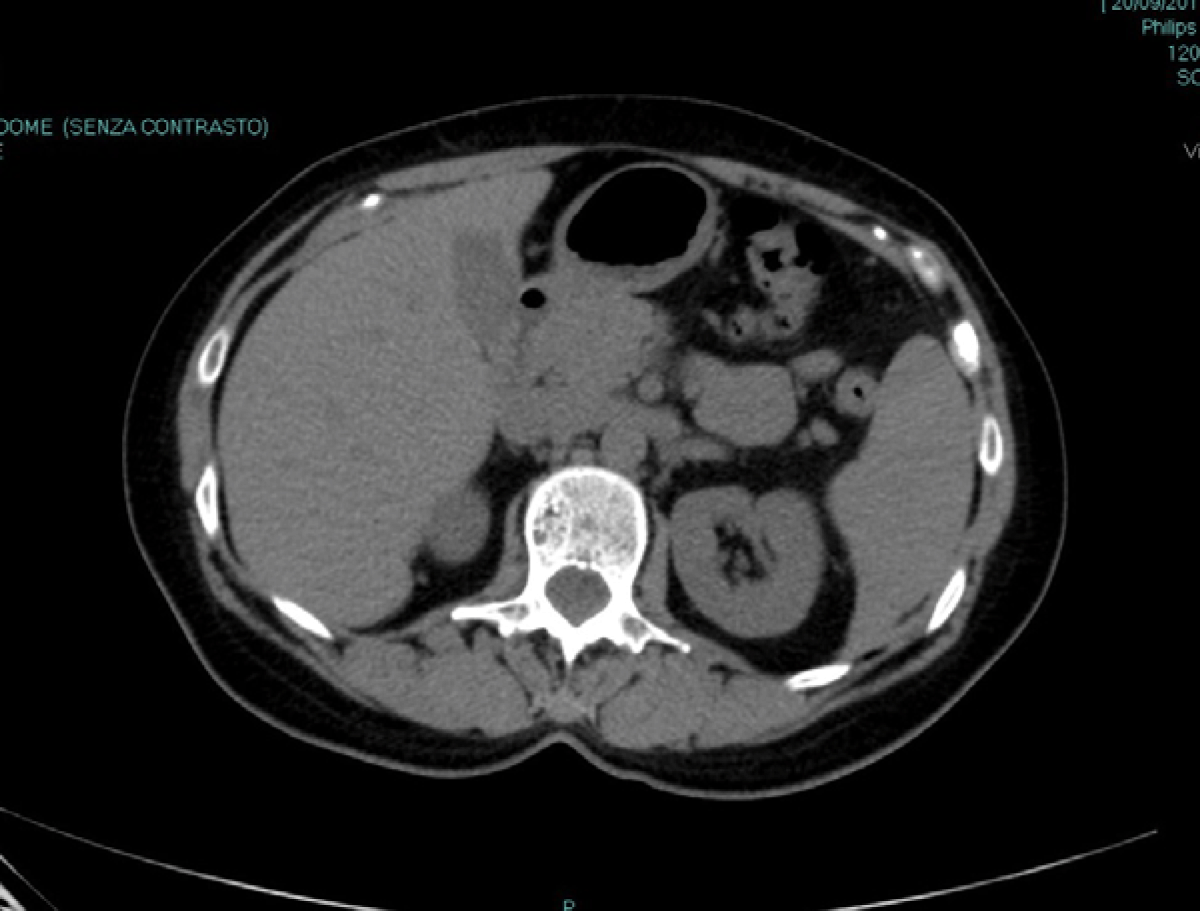

General conditions were good and vitals were normal. Physical examination revealed an area of tenderness at the upper left quadrant of the abdomen, without any guarding or rebound, where a deep mass could be palpated. Urine test and culture were negative. Blood test showed no abnormality, in particular no anemia or eosinophilia. Serologic tests for parasites were negative. Ultrasound scan revealed an 8-cm cystic mass of the spleen but no free fluid. Computed tomography (CT) scan (Figure 1) confirmed the presence of an 8-cm cyst of the medial aspect of the spleen without any other relevant abdominal finding. The cyst was apparently simple and thin-walled, without any internal sept or vegetation. The CT scan was unenhanced as patient declined contrast.

Figure 1: Basal unenhanced abdominal computed tomography scan showing an 8-cm non-parasitic splenic cyst.